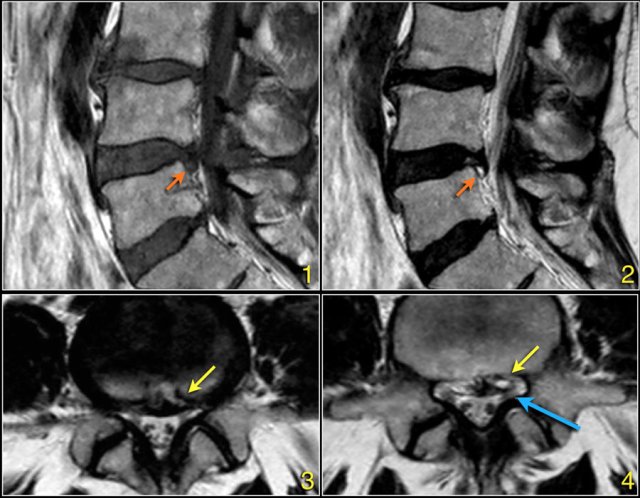

The signal intensity of a hernia on T1W-images is usually intermediate, while on T2W-images it can be a high signal fresh herniated nucleus pulposus or a somewhat older low signal intensity hernia.

Here a herniation with high signal (yellow arrow on transverse images) sliding through the annular tear and compressing the left L5 nerve (blue arrow).

Here a patient with severe arthrosis of the facet joints.

Notice that there are many synovial cysts related to the arthrosis (red arrows).

At the L5S1 level a large cyst on the right compresses the S1-nerve (yellow arrow).